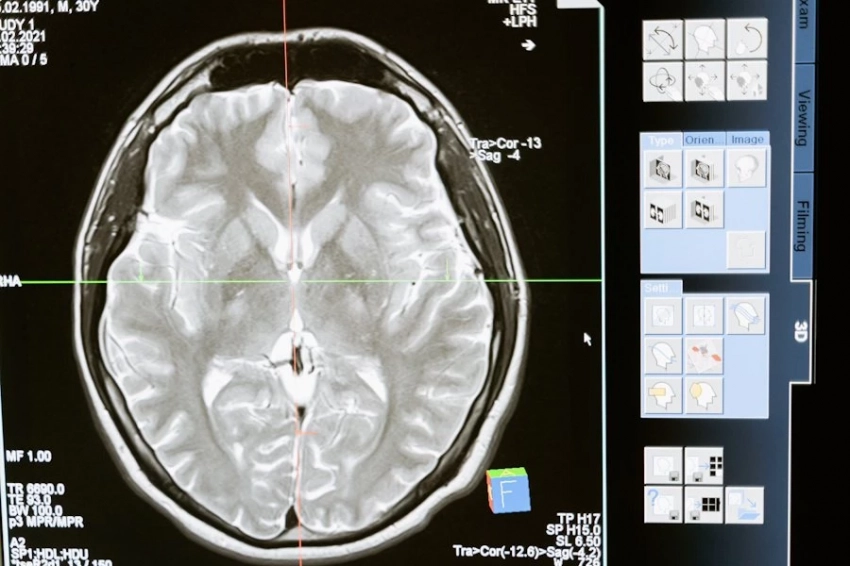

Научный журнал Cell Reports Medicine рассказал об исследовании группы специалистов Мадридского института онкологии, совершивших знаковое открытие в области противораковой терапии.

Профессор Гильермо Эстебан Сантильяна, ведущий специалист исследования, в кооперации с коллегами выявил механизм, который делает возможным контроль агрессивного поведения злокачественных клеток через воздействие на особый белок – интегрин-альфа.

Главный автор проекта профессор Сантильяна поделился некоторыми подробностями. Рассказал, что группе удалось выявить: через подавление активности интегрин-альфа происходит существенное снижение способности опухолевых клеток к миграции. В условиях  лабораторных экспериментов экспертам удалось добиться 70-процентного уменьшения метастатической активности.

Тестирование проводилось на трехмерных клеточных моделях, при помощи которых имитировались реальные опухоли. Исследователями была применена инновационная методика визуализации, позволяющая в реальном времени осуществлять наблюдение за поведением мутировавших клеток.

Испанскими учеными был разработан экспериментальный препарат, способный блокировать работу интегрин-альфа. Они провели доклинические испытания на лабораторных животных, показавшие многообещающие результаты: у подопытных особей зафиксировали заметное замедление роста опухолей. К тому же, лекарство не даёт ощутимых побочных эффектов, отмечают авторы новации.